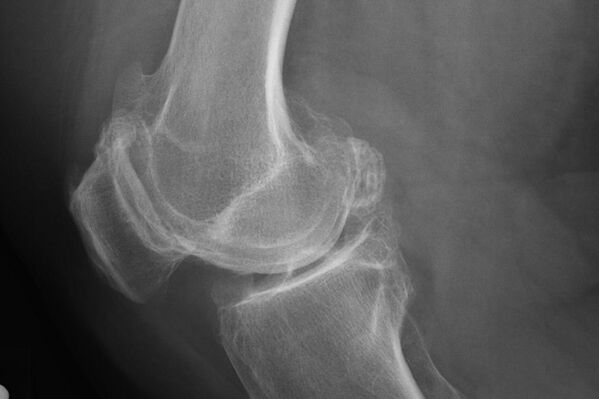

X -Ray kartilagoan desbideratzeak identifikatzen lagunduko du.

Azterketaren ostean, medikuak gaixoaren erradiografia agintzen du. Hau da edozein graduko belauneko artikulazioaren artrosia diagnostikatzeko metodo nagusia.

X -Ray-k medikuak artikulazioaren kartilagoan gertatzen diren aldaketen ideia ematen dio. Hala ere, zenbait kasutan, hasierako etapa ezin da irudian zehaztu.

Beharrezkoa bada, medikuak X izpien edo erresonantzia magnetikoaren tomografia errepikatua eman dezake.